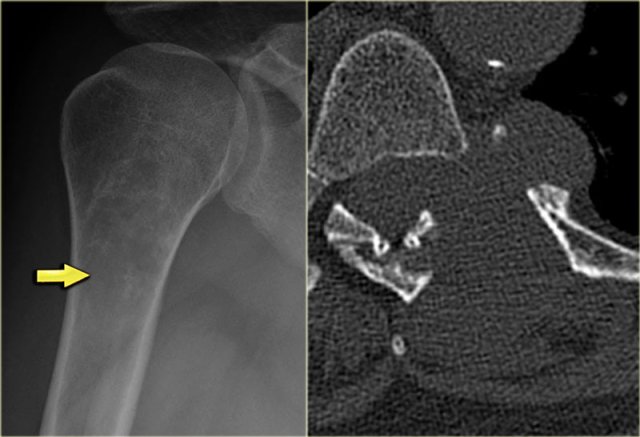

On the left an ill-defined lytic lesion in the femur of a young patient.

There is a permeative destruction pattern with irregular cortical destruction.

There is an aggressive periosteal reaction (arrow).

This is also called sunburst appearance.